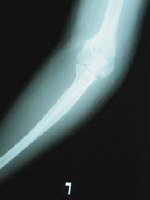

X線所見 :正面及び斜位において、左上腕骨外顆を縦方向に貫通する骨折線が認められる(図1,2)。側面では、骨折線が不明瞭。

図2 受傷時X線 側面像 |